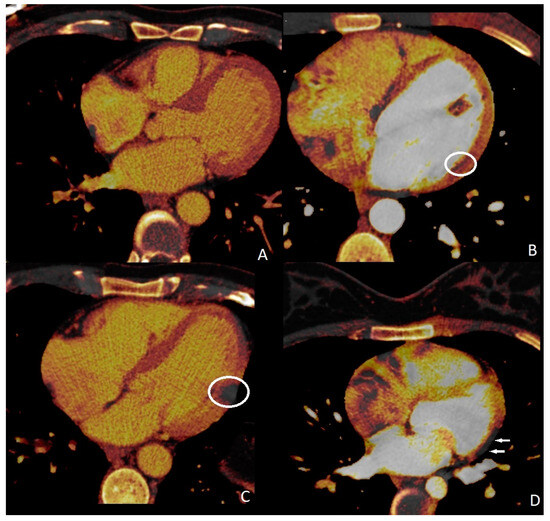

Perfusion deficits were found on DECT iodine map images with a subendocardial (n = 4, 30.7%), subepicardial (n = 7, 53.8%), and transmural (n = 2, 15.3%) anatomical location within the left ventricular wall (Figure 3). Subendocardial involvements were found in the patients who had obstructive CAD, and PDs correspond to associated coronary artery territories. Subepicardial and transmural PDs did not correspond to any coronary artery territories. ROI was used to measure the perfusion deficit and normal areas on the iodine map images on DECT. The mean value of the perfusion deficit areas was 162.13 ± 21.31 HU (range, 45–294), while that of the normal areas was 50.11 ± 9.32 HU (range, 23–91).

Figure 3.

Myocardial perfusion maps. Normal (A) perfusion image, subendocardial ((B), circle), transmural ((C), circle), and subepicardial ((D), arrows) perfusion deficits.